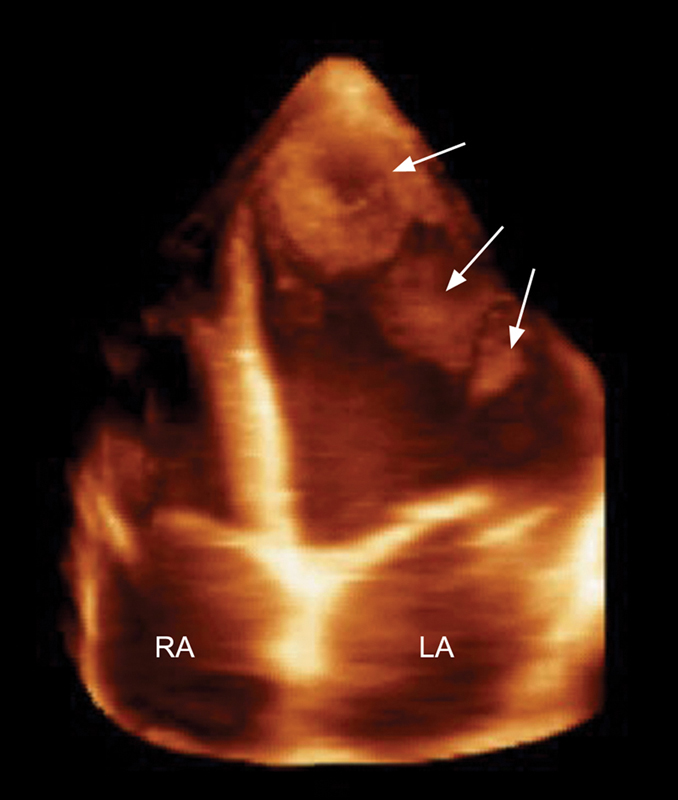

فحوصات تشخيصية لبعض امراض القلب والشرايين التاجية